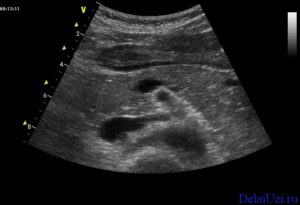

Методика проведения УЗИ поджелудочной железы

Сонография поджелудочной железы является полностью безболезненной и высоко информативной, доступной процедурой для большинства пациентов. Кроме того занимает совсем мало времени – около десяти минут. Нужно освободить от одежды область живота, именно на эту область врач будет наносить специальный гель, который называется медиагель. И потом будет проводить обследование УЗ-датчиком.

Больной должен лежать спокойно, поначалу на спине, а позже, с разрешения врача, повернуться на правый и левый бок, чтобы изучить поджелудочную железу со всех сторон. Врач-УЗИст осматривает железу при задержке дыхания на вдохе по максимуму и при спокойном дыхании пациента.

При проведении данной процедуры изучаются положения поджелудочной железы относительно сосудов и позвоночного столба, строения панкреатических протоков и самой железы, формы и размеры.